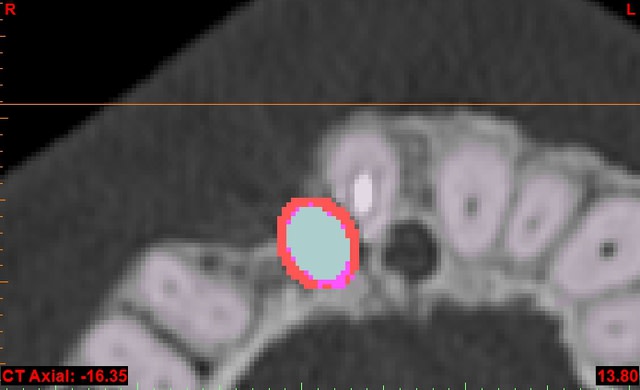

en attendant, voici un autre cas de "OUPS L'IMPLANT" adressé par un confrère...